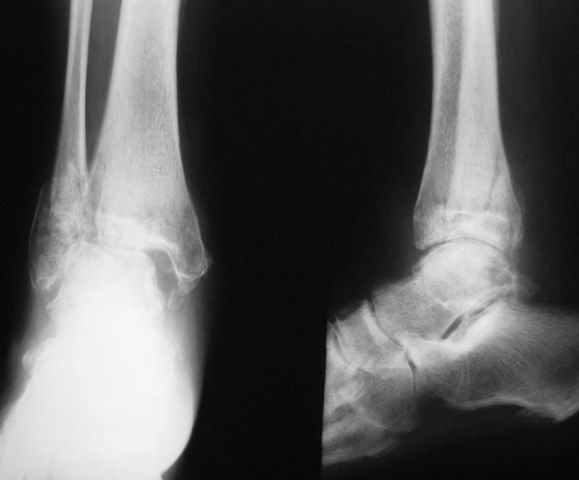

Если принять в качестве причины развития инфекции в области внутренней лодыжки трофические нарушения обусловленные неустраненным подвывихом стопы, то можно предположить что его устранение улучшит ситуацию. На представленной фотографии данных за гнойный артрит нет, имеется местное нагноение мягких тканей. Я бы попробовал накостный остеосинтез малой берцовой и мощный болт стяжку проведенный через отверстие в пластине на медиальную поверхность вне зоны инфекции, с обязательным дренированием и ревизией инфицированной области.

>Я бы попробовал накостный остеосинтез малой берцовой и мощный болт стяжку проведенный через отверстие в пластине на медиальную поверхность вне зоны инфекции, с обязательным дренированием и ревизией инфицированной области.(Александр Н.)

Суть вопроса заключается не как добиться хорошей рентгенограммы, а что действительно улучшит качество жизни пациентке. Если после остеосинтеза (берем идеальный вариант течения событий) у нее сохранятся боли, будет ограничение движений, и через пару лет опять встанет вопрос об артродезе, то стоит ли оно того?